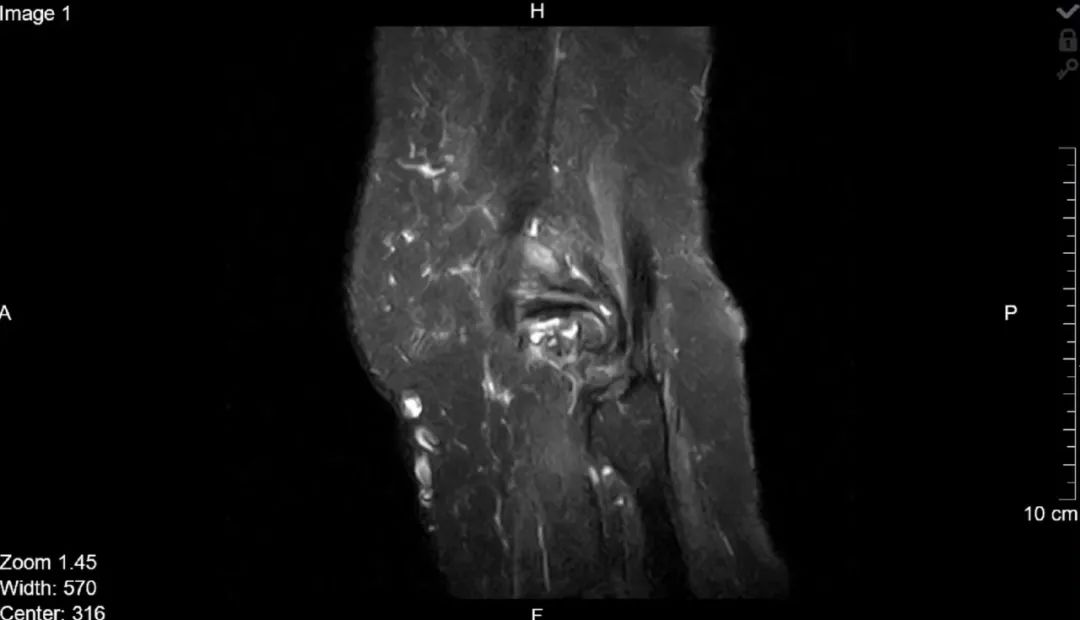

对于人体中的核磁共振成像,通常以氢核为目标,因为其中水和脂肪中有很多,然后图像的亮度基本上可以告诉我们脂肪和水的数量。人们也可以瞄准其它原子核并进行测量,这就导致了不同核磁共振图像的工作方式不同。核磁共振成像非常适合于检查软组织,而对于骨折一般则使用X射线成像。